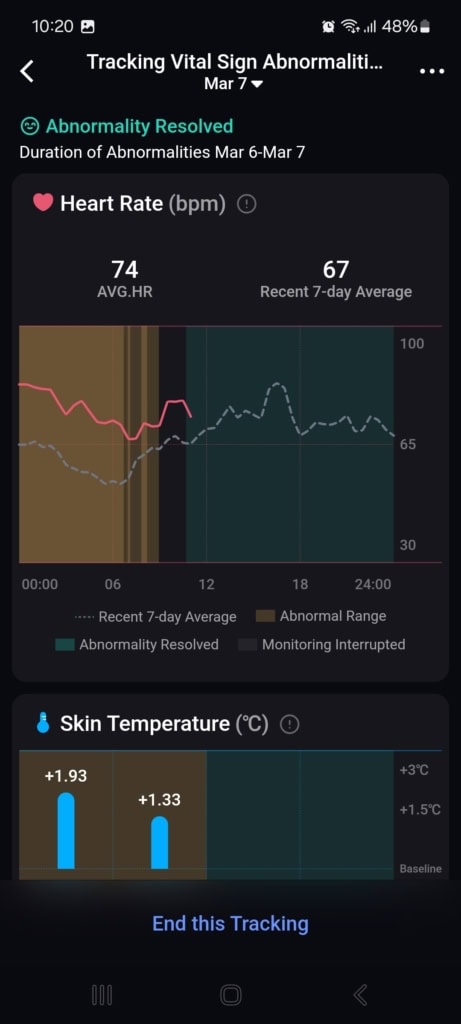

Stan funkcji życiowych (Znaki życia)

W tej części aplikacji dowiesz się o całodziennych wahaniach tętna i jego zmienności, nasyceniu krwi tlenem, częstotliwości oddechów podczas snu i temperaturze snu. Aplikacja porównuje wszystkie te dane z twoją własną referencją z ostatnich 7 do 30 dni oraz z referencyjnymi wartościami medycznymi. Gdy tylko w ciągu dnia lub nocy osiągniesz wartości, które nie mieszczą się w referencyjnych granicach, aplikacja cię o tym poinformuje.

Najczęściej spotykałem się z wyraźnym spadkiem zmienności tętna i wzrostem samego tętna. Te wahania pojawiały się czasem podczas snu, aktywności sportowej lub w przypadkowych sytuacjach, o których nie miałem pojęcia. Mimo że doceniam ten kompleksowy wgląd w moje funkcje życiowe, brakowało mi podczas testowania kontekstu. Funkcja oferuje jedynie wartości i spostrzeżenia, że coś jest nie tak. Nie znalazłem w aplikacji żadnych wskazówek dotyczących możliwych przyczyn ani rekomendacji działań, które mogłyby pomóc przywrócić stan do normy.

Mimo że nietypowe wartości nie mają jasnego kontekstu, aplikacja zwraca na nie uwagę i pyta, co mogło być ich przyczyną (spożycie alkoholu, infekcja, kofeina i inne). W moim przypadku działało to idealnie. Popełniłem błąd dietetyczny, przez który dostałem gorączki i problemów trawiennych. Mój ogólny stan znacznie się pogorszył, co objawiło się wyraźnym spadkiem jakości snu, obniżoną zmiennością tętna i podwyższoną temperaturą ciała. Wszystkie te zmiany zostały przez pierścień i aplikację trafnie rozpoznane i ocenione. Po kilku dniach mój stan się poprawił – również to zostało odnotowane i odpowiednio skomentowane.